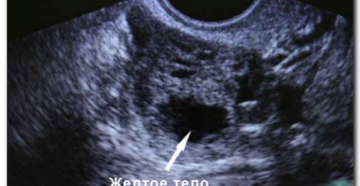

Желтое тело на УЗИ в яичнике после овуляции — что означает и как выглядит? Главным…